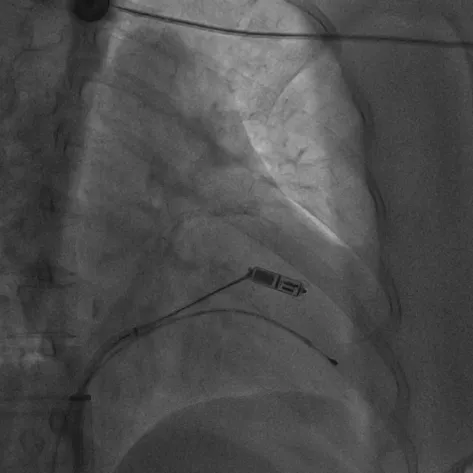

无导线起搏器被抓捕、拔除的术中影像

治疗团队经过充分讨论并评估了手术风险及预后,与家属反复沟通,决定为张女士实施无导线起搏器移除+生理性起搏+心脏再同步除颤器(LOT-CRTD)植入术。术前,汤宝鹏教授带领治疗团队进行了详细的文献查阅和充分的病情评估,对术中可能出现的各种风险做好了应急预案。术中,手术团队使用圈套器成功抓捕无导线起搏器Micra尾端并顺利拔除,同时给患者植入左束支心脏再同步起搏除颤器。手术顺利,患者术后恢复良好。